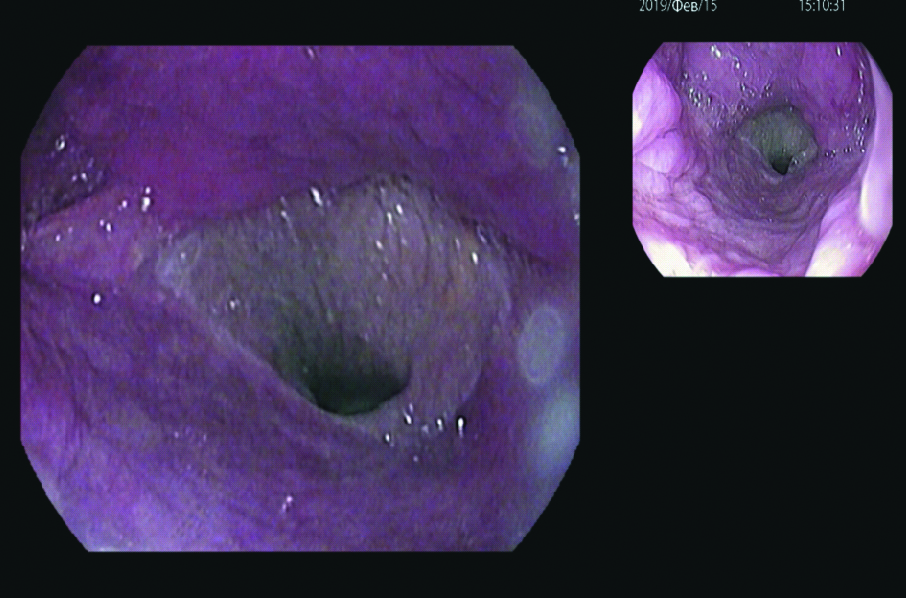

During endoscopic monitoring, no signs of anastomotic leakage were detected (Fig. 10).

Figure 10. The endoscopic image. The adapted radial flap was fully integrated in the defect area